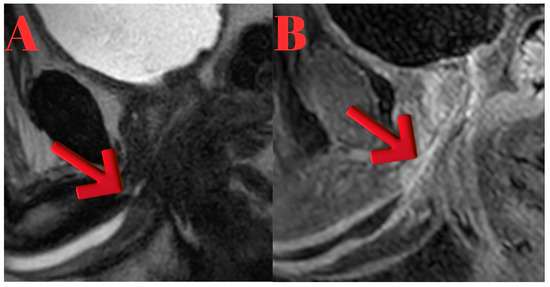

Background/Objectives: Conventional imaging modalities are often inadequate for evaluating the proximal extent of anterior obliterative urethral strictures. Magnetic Resonance Imaging (MRI), with its superior soft tissue resolution, provides detailed anatomical insights and significantly contributes to surgical planning in such cases. Methods: Four male patients aged 26–63 years with anterior obliterative urethral strictures were evaluated using MRI in addition to conventional imaging. All MRI scans were performed following a modified Joshi protocol. Clinical data, MRI findings, and surgical outcomes were retrospectively reviewed. Results: MRI successfully delineated stricture length, location, periurethral fibrosis, and proximal urethral status in all cases, correlating well with intraoperative findings. Case 1 showed a 2 cm proximal bulbar obliteration, excised with end-to-end anastomosis. Case 2 had a 2.5 cm distal bulbar stricture, managed similarly. Case 3 revealed multi-segmental strictures, treated with a combination of anastomosis, graft, and Kulkarni urethroplasty. Case 4 demonstrated a rare 9 cm distal penile obliteration with preserved proximal urethra, treated with anastomotic repair. MRI provided critical anatomical detail for surgical decision-making. Conclusions: MRI is a valuable imaging modality for the evaluation of anterior obliterative urethral strictures, particularly when the proximal extent of the stricture cannot be visualized with conventional imaging techniques. In our case series, MRI enabled precise delineation of the stricture length and surrounding anatomical structures, which was critical for selecting the most appropriate surgical approach. Full article

Figure 1